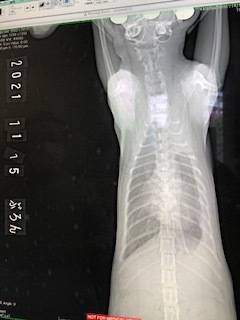

11月15日 治療29日目 5週目通院

レントゲン検査

左肺もさらに黒い部分が増え酸素が入ってきています。

エコー検査(1ヶ月おき)

体重 1.94kg 投薬量250mg